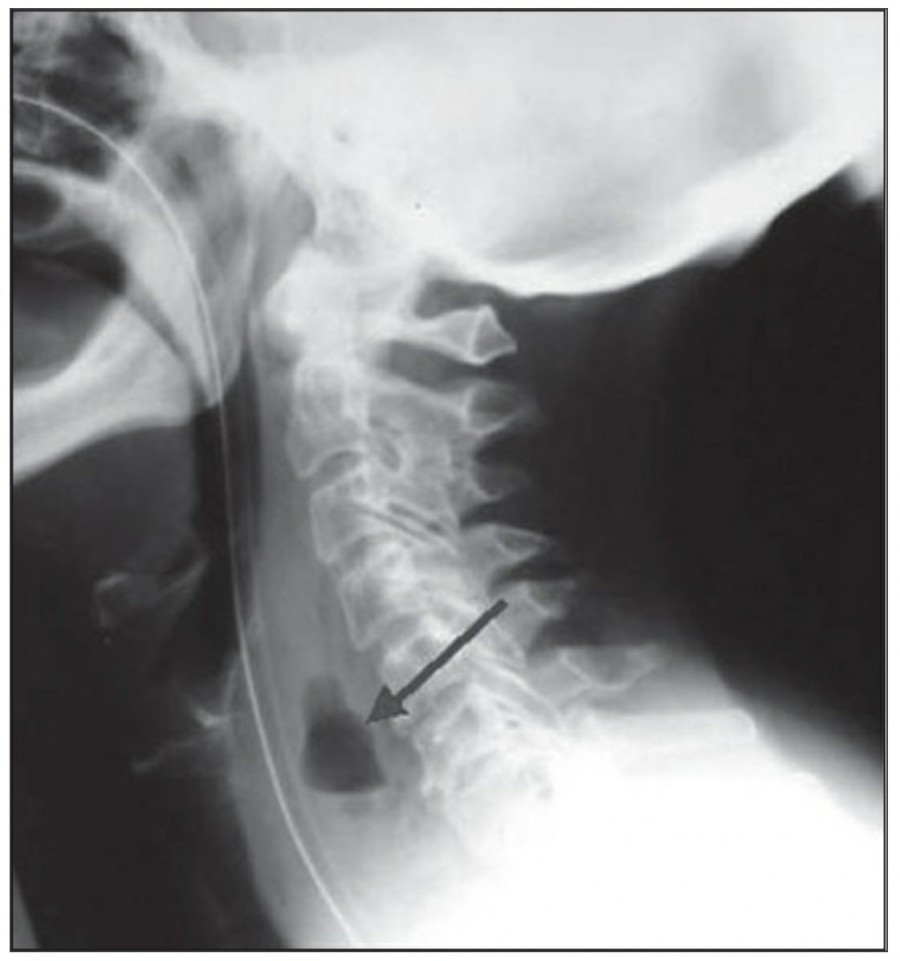

Upper airway 손상이 의심될 때, lateral radiograph 촬영이 유용하다. Trachea와 cervical spine 사이 soft tissue space의 지름이 vertebral body 1개의 넓이보다 증가한다면 혈종이나 감염이 원인일 수 있다.

Pneumothorax, pneumomediastinum, subcutaneous emphysema in the neck or precipitous respiratory failure following intubation 등에서는 trachea rupture와 같은 중한 손상을 의심해 볼 수 있는데, trachea rupture는 주로 posterior 쪽에 위치한다.